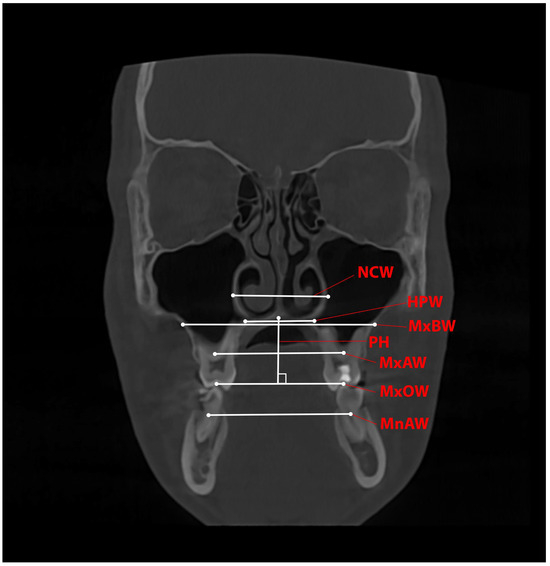

Changes and Correlations Between the Width and Height of the Hard Palate During Rapid Maxillary Expansion with a Printed Tooth-Borne Expander

Background/Objectives: The nasomaxillary complex is a compound anatomical structure in which the correlation between changes in palatal width and height has been poorly investigated. Methods: A three-year prospective study with 28 patients treated with printed expanders was conducted. Measurements on CBCT images were performed before and after treatment; the width and height parameters were measured on a coronal slice of a CBCT image at the level of the first molars and upper first molar inclination relative to the palatal plane. Results: A significant difference was found between the values measured before and after treatment, including an increase in the measured width parameters and a statistically significant decrease in palatal height (0.75 ± 0.97). The mean change in the upper molar inclination was not significant (tooth 16: 0.60 ± 6.42; tooth 26: 2.19 ± 4.51). The regression analysis did not establish a significant correlation between the expansion of the maxillary occlusal width and palatal height change or a significant correlation between the increase in the upper molar inclination and palatal height change. Conclusions: The use of a printed tooth-borne expander causes predictable and reproducible skeletal changes. It is a feasible treatment option, allowing for precise screw positioning to achieve bodily movement of the teeth and decrease the change in molar inclination. Full article